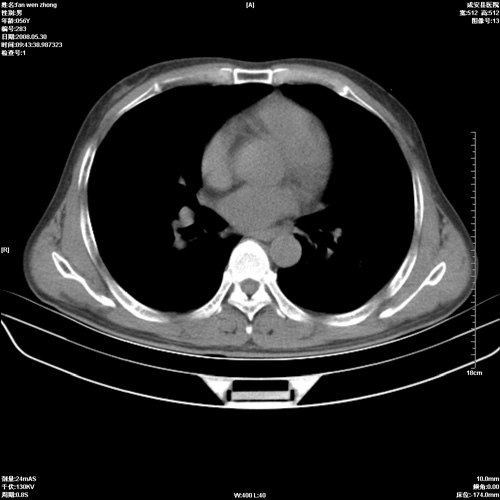

病人 男 56岁 一周前高热,体温达39-40度,经抗炎治疗后,体温渐降,达37,5-38度,轻微咳嗽,胸部不适 查白细胞为1.3万 行ct检查,请分析。

双肺内可见多发结节状病灶,并见小空洞,病人高热,白血球增高,应该是典型的迁徙性肺脓肿(多为金黄色葡萄球菌感染)。查一下口腔等其它部位有无感染灶。

双肺内可见多发结节状病灶,并见小空洞,病人高热,白血球增高,应该是典型的迁徙性肺脓肿(多为金黄色葡萄球菌感染)。建议治疗后复查.